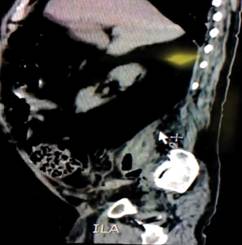

Presentamos el caso de un masculino de 68 años con antecedente de enfermedad de gota de larga evolución, en tratamiento con ketorolaco (30 mg vía oral cada ocho horas). Su padecimiento inició en enero de 2017 con dolor opresivo 7/10 en la fosa iliaca derecha -que cedió parcialmente a la administración de ketorolaco (en la dosis ya mencionada)-, acompañado de náuseas y vómito. Tras cinco días de evolución sin lograr remitir los síntomas e incrementando en intensidad 9/10, ingresó al Servicio de Urgencias del Instituto Mexicano del Seguro Social núm. 1 de Cuernavaca, Morelos. En la exploración física lo encontramos orientado en sus tres esferas, alerta y cooperador, con buena coloración de tegumentos, con facies dolorosa; abdomen globoso a expensas de panículo adiposo, peristalsis disminuida, resistencia abdominal voluntaria, miembro pélvico derecho en flexión voluntaria antiálgica y doloroso a la extensión. Signos de McBurney, del obturador y Markle, positivos. La biometría hemática mostró leucocitosis de 20,000/mm3, 3,800 monocitos/μl, 14 neutrófilos/mm3; esto nos dio la orientación clínica hacia una apendicitis, con una puntuación de Alvarado de 7. La tomografía axial computarizada (TAC) mostró una imagen líquida a nivel del músculo psoas derecho en el retroperitoneo (Figuras 1 y 2), lo cual modificó el diagnóstico y nos orientó hacia un absceso del psoas derecho de origen primario, al no encontrar datos de una infección previa. Se programó para una cirugía de drenaje. Durante la cirugía se observó una colección de líquido en el músculo psoas derecho de 300 ml aproximadamente que se drenó sin complicaciones por cirugía abierta mediante punción directa del absceso. Se dejó Penrose para el drenaje de secreciones, y una vez terminado el acto quirúrgico, se ingresó a piso con manejo antibiótico con ceftriaxona a razón de 1 g IV cada 12 horas durante su estancia hospitalaria. Al quinto día postquirúrgico inició con disnea, distensión abdominal, eventración de la herida quirúrgica y presencia de cambios necróticos, por lo que ingresó nuevamente al quirófano para realizarle una laparotomía exploradora; en el transoperatorio se localizó una perforación de sigmoides que condicionaba una fascitis necrosante con extensión a la pared y fascia retroperitoneal. Se realizó un lavado quirúrgico y desbridación de tejido necrótico, y se colocó una bolsa de Bogotá. Al siguiente día postquirúrgico inició con datos de choque séptico y falla orgánica, con un SOFA de 12 puntos. Su evolución fue tórpida; falleció 25 días después por falla orgánica múltiple.

Figura 1: TAC, corte sagital; se observa una imagen del retroperitoneo ocupado por líquido a nivel del músculo psoas iliaco.

El absceso del psoas es más frecuente en varones en la edad media de la vida. Es una patología poco frecuente; sin embargo, el uso de la TAC ha incrementado la frecuencia del diagnóstico;3 en nuestro caso, la TAC nos permitió llegar al diagnóstico de absceso del psoas.

La prueba diagnóstica de elección en la actualidad es la TAC, ya que la sensibilidad de dicha prueba es cercana al 95%.7 Fue gracias a la TAC que se logró tener una orientación diagnóstica mejor, al observar en la imagen la presencia de líquido en el retroperitoneo.